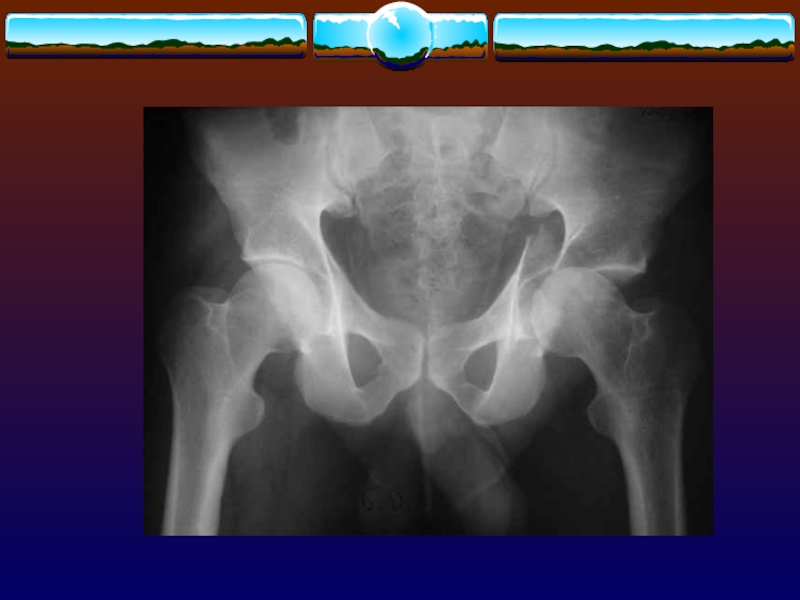

Слайд 97Объективное исследование

пульс на бедренных артериях

осторожно и только один раз

исследуют таз, чтобы определить нестабильность тазового скелета,

осуществляя компрессию в следующих

направлениях и оценивая любую степень «податливости»

-от латерального края в медиальном напрвлении на уровне подвздошных гребней

-спереди назад на лобковый симфиз

-спереди назад на уровне подвздошных гребней

манипуляции прекращают при первых признаках нестабильности

Объективное исследование пульс на бедренных артерияхосторожно и только один раз исследуют таз, чтобы определить нестабильность тазового скелета,осуществляя